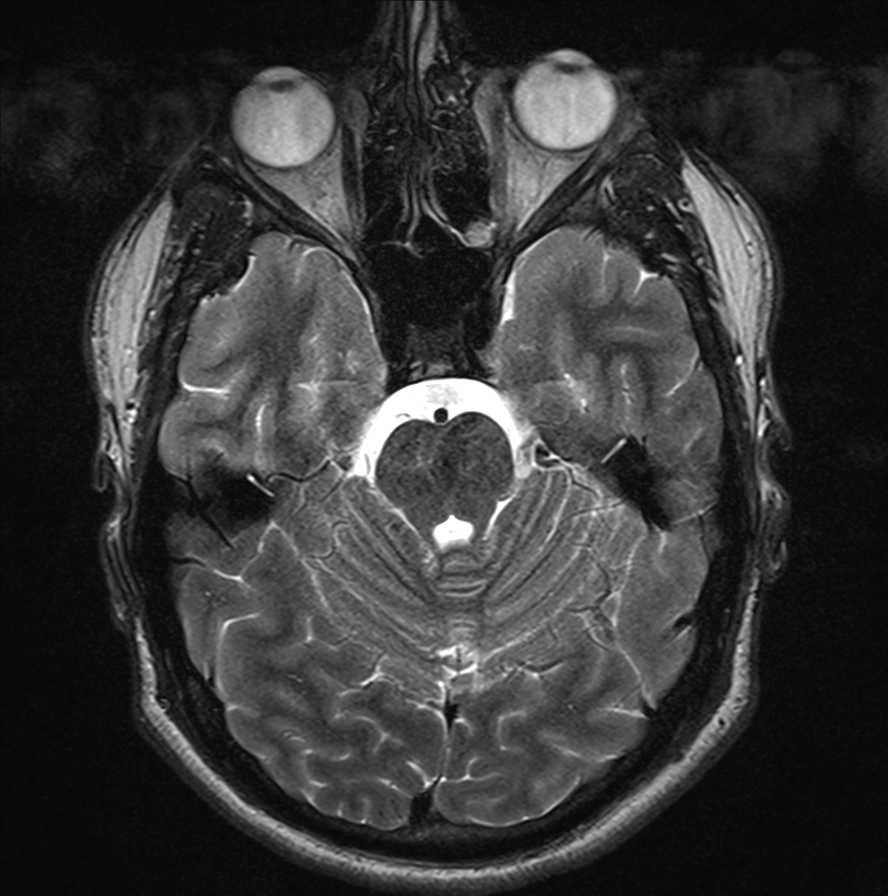

So this is what you get out of it (these pictures aren't mine though!) Which is pretty fascinating to look at.